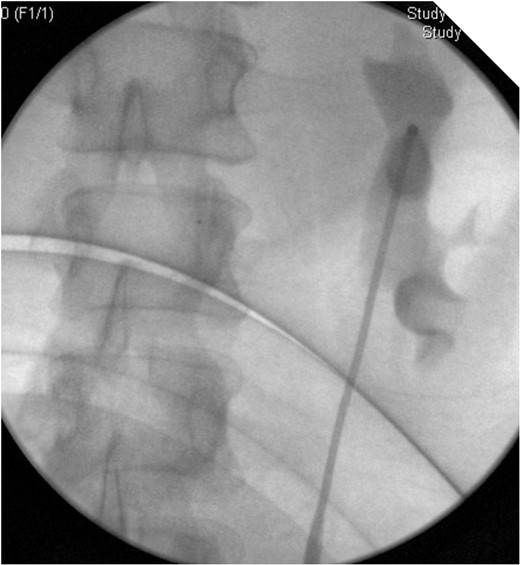

CT IVU- confirmed extravasation of contrast medium around the left kidney and ureter, the rupture being at the level of the PUJ.

Coronal view reconstructions using maximum intensity projection, showing proximal ureteric leak of contrast.

Blood tests, clinical parameters and temperature were still well within normal limits, despite the severity of symptoms and clinical examination. We opted to treat her with retrograde endoscopic ureteric stent insertion. A 6-French long-term stent was inserted uneventfully across the defect. A 16 F urethral catheter was inserted to avoid reflux. The patient was also started on intravenous ciprofloxacin and piperacillin/tazobactam post operatively.